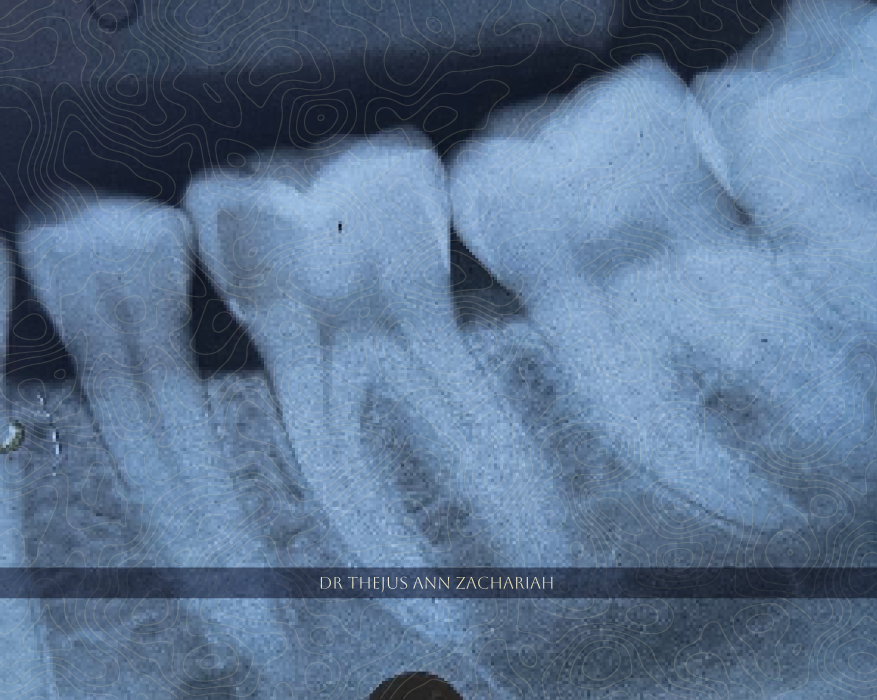

Partial PulpotomyPre-Operative Caries Excavation With Mesial Pulp Exposure Partial Pulpotomy Hemostasis Achieved MTA Vital Pulp Therapy Post-Operative Non Vital Intracoronal Bleaching - 11Vital Overlay - 36